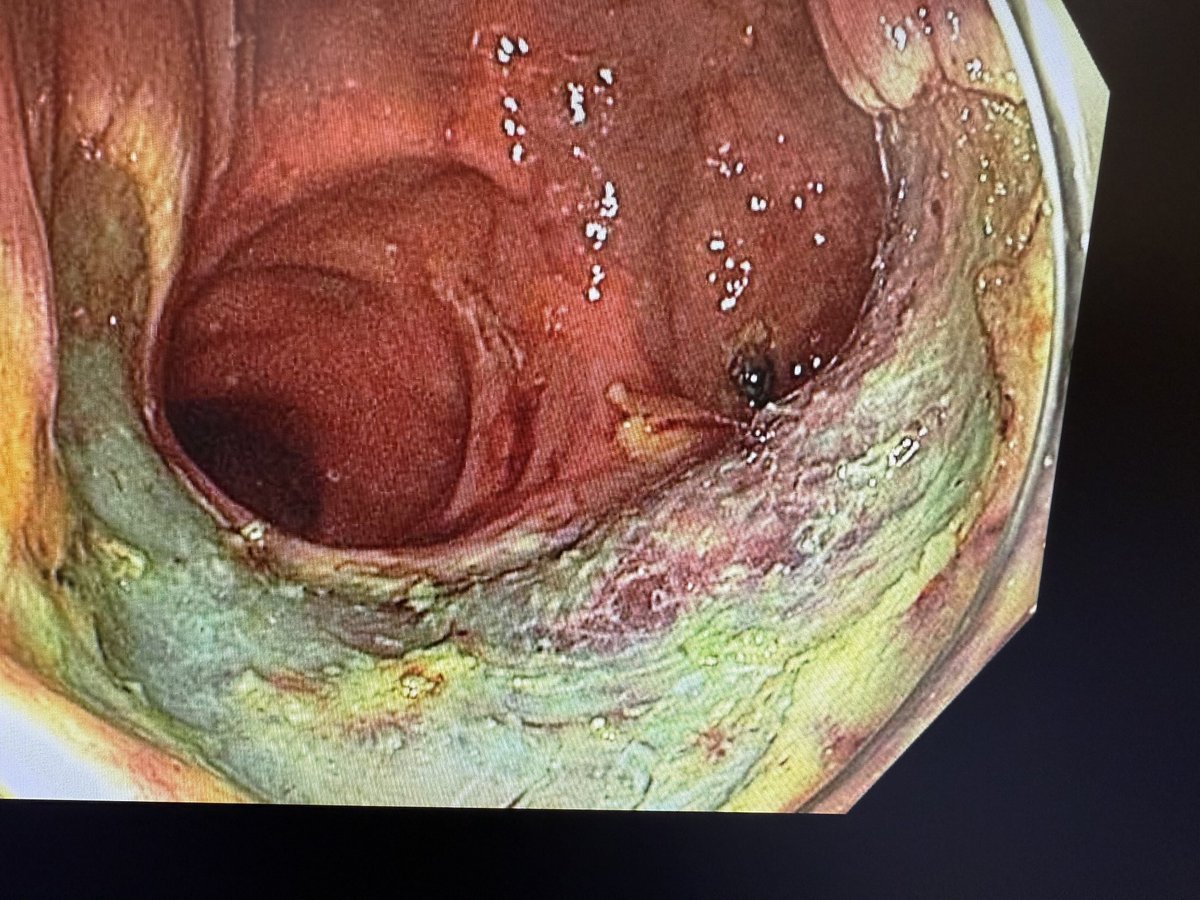

Delighted to share a MAJOR milestone in minimally invasive cancer treatment. We just completed the *first* Pharyngeal ESD in North America at @KingstonHSC . Huge thanks to the GI endoscopy team, @QueensuDOM, @SEAMOKingston for your endless support